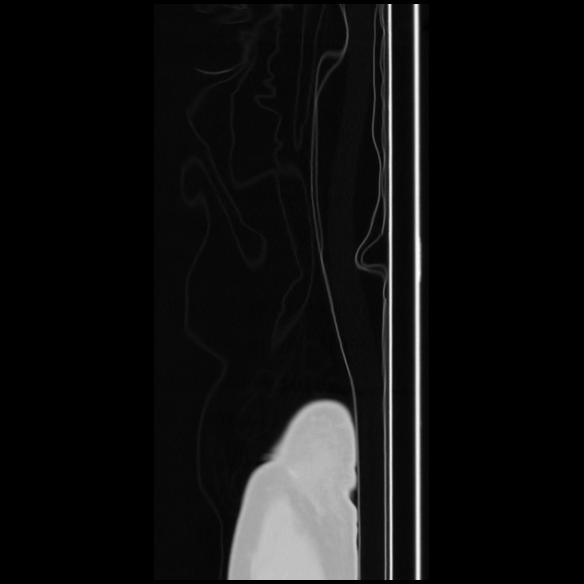

7 CUERPO,CE,Sagittal,3.000,CUERPO,Sagittal,